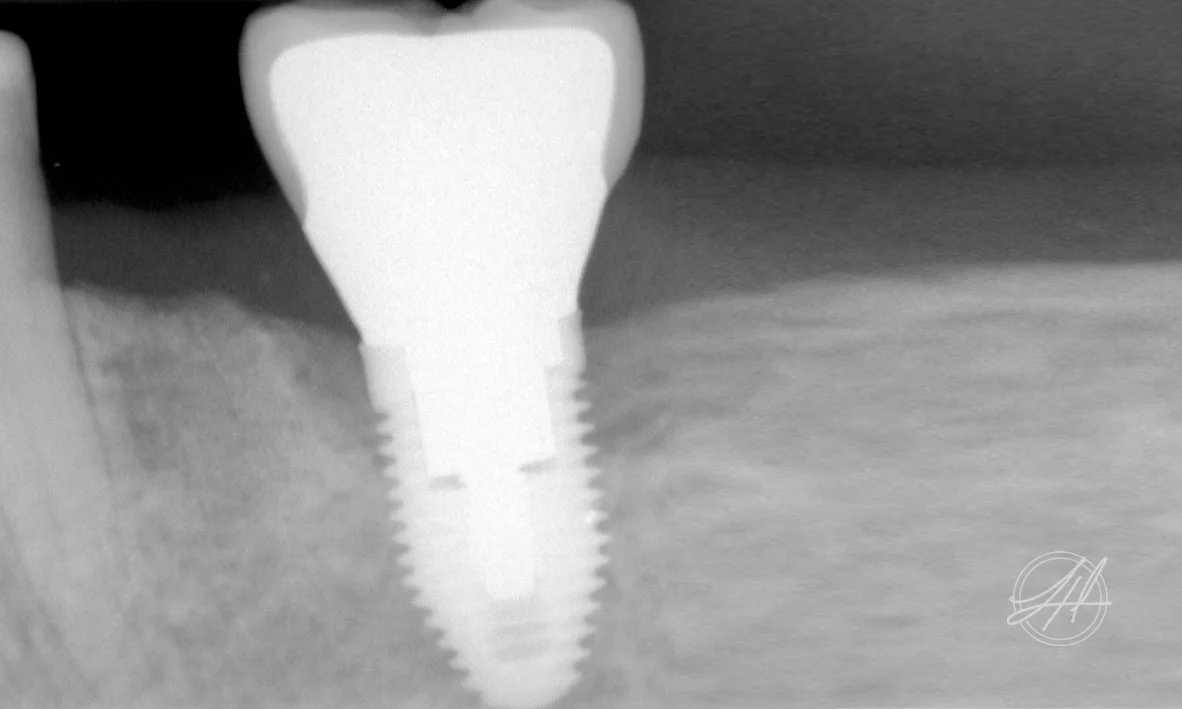

Dental Implant Diseases

For some patients, metal roots are surgically implanted in to the jawbone to replace missing or extracted teeth. False teeth are then attached to the implants in the form of a crown or bridge. Over time, the bone and gum grow around the implant and hold it in place. These tissues are extremely delicate and require regular professional check-ups and meticulous ongoing cleaning by patients.

Dental implant (peri-implant) disease occurs when bacteria builds up around the dental implant. This inflames the gum and once it builds up your immune system attempts to get rid of it through inflaming the gum around the implant.

Peri-implant disease can cause long term damage such as bone loss and exfoliation (loss) of implants. Such damage may be accelerated by a factors such as poor oral hygiene, ill fitting dental crowns and bridges, smoking, diabetes and untreated periodontitis.

PERI-IMPLANTITIS

Peri-implantitis can be a fast, self-progressing oral disease, presenting as advanced inflammation of the gums and supporting bone surrounding the implant.

It is caused by by certain bacteria (the same periodontal bacteria) and by the local inflammation triggered by those bacteria. These periodontal bacteria are naturally present in the mouth however, they become harmful when conditions are favourable for them to grow in numbers, altering their pathogenicity.

More dangerous bacteria are able to thrive and multiply, which produce harmful by-products. These then stimulate the body’s defensive inflammatory response in the gums. When the disease progresses, chronic inflammation causes the bone of the jaw to be destroyed and the implants can be lost. This process is commonly gradual, occurring over 3 to 5 years post-surgery of the implant.

Peri-implantitis can be treated with advanced and sophisticated surgical procedures, if detected early.